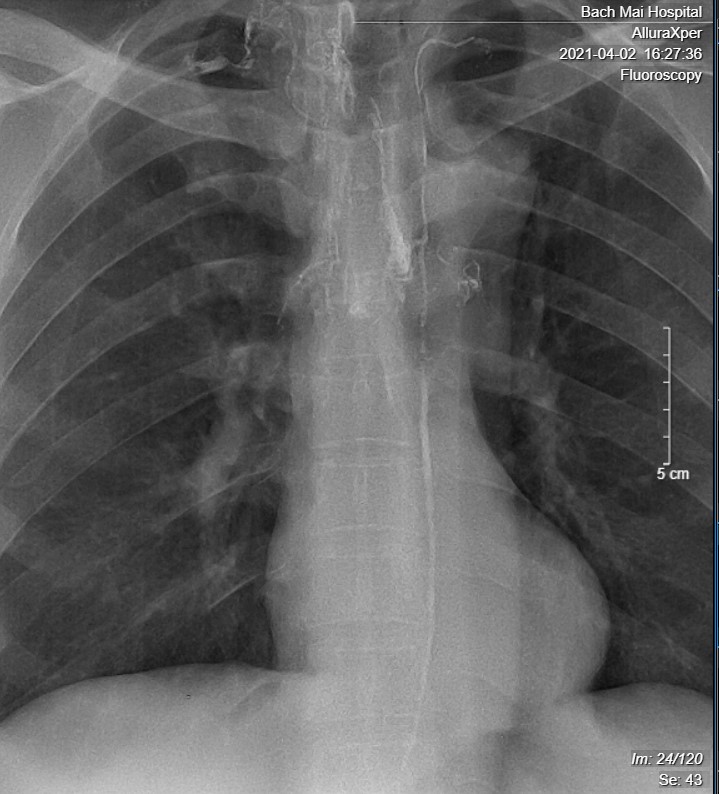

Ảnh 3. Chụp bạch mạch DSA cho thấy ống ngực có hình thái bình thường, đổ vào tĩnh mạch dưới đòn trái. Lipiodol tràn vào bạch mạch trung thất.